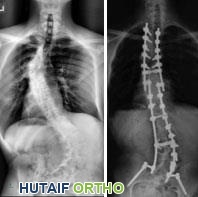

• الجنف (Scoliosis): الجنف هو انحناء جانبي في العمود الفقري. بدلاً من الخط المستقيم في منتصف الظهر، ينحني العمود الفقري المصاب بالجنف، وأحيانًا يبدو كحرف S أو C.

• أنواع الجنف في NF1: يمكن أن يتراوح الجنف لدى الأطفال المصابين بـ NF1 من انحناءات خفيفة إلى شديدة. في العديد من الحالات، تتطور منحنيات العمود الفقري ببطء، بمعدل مماثل للمنحنيات التي تُرى في الأطفال المصابين بالجنف مجهول السبب. يُطلق على هذا النوع من الجنف لدى الأطفال المصابين بـ NF1 اسم "الجنف غير التخريبي" (nondystrophic scoliosis). ومع ذلك، يمكن أن يحدث تغير في الشدة، مما يؤدي إلى تغيرات تخريبية.

• الجنف التخريبي (Dystrophic Scoliosis): الشكل الأقل شيوعًا من الجنف الذي يصيب الأطفال المصابين بـ NF1 هو الجنف التخريبي. نمط الانحناء في هذا النوع من الجنف قصير وحاد مع تحدب مصاحب (تقوس الظهر). يوجد أيضًا ترقق في الأضلاع، بالإضافة إلى تكون غير طبيعي للفقرات بسبب أورام جذور الأعصاب أو تضخم الكيس الجافوي داخل القناة الفقرية. يمكن أن تتفاقم هذه المنحنيات بسرعة وتؤدي إلى تشوه خطير.

• الحداب (Kyphosis): بالإضافة إلى ذلك، قد يعاني الأطفال المصابون بـ NF1 من الحداب كتشوه رئيسي في العمود الفقري.

منحنى الجنف

(يسار) تشريح العمود الفقري الطبيعي. (يمين) يمكن أن يجعل الجنف العمود الفقري يبدو أشبه بحرفي "C" أو "S".